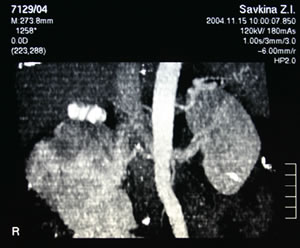

КТ

органов брюшной полости, забрюшинного пространства: |

|